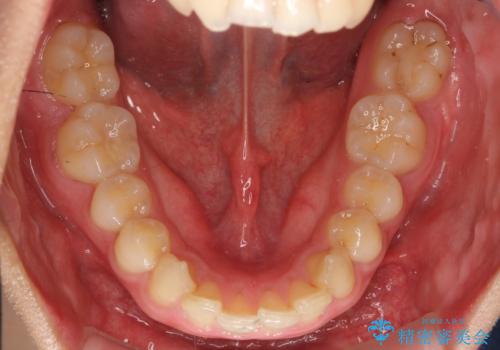

深いかみ合わせ 出っ歯の治療 インビザラインで

- 前歯の前突を主訴に来院。

かみ合わせが深く、また奥歯のかみ合わせも全体的に上が前にずれていました。

抜歯矯正も難しく、非抜歯矯正も歯の移動量が多くいずれにしても難易度が高い状態でした。

時間はかかりますが非抜歯で治療することにして、インビザライン矯正とワイヤー矯正を交互に行い仕上げました。

インビザライン矯正だけでなく、途中ワイヤー矯正もはさみました。前歯のかみ合わせが深く、本当に大変な治療でしたが協力度も高く非抜歯で上の奥歯を後ろに動かすことができました。